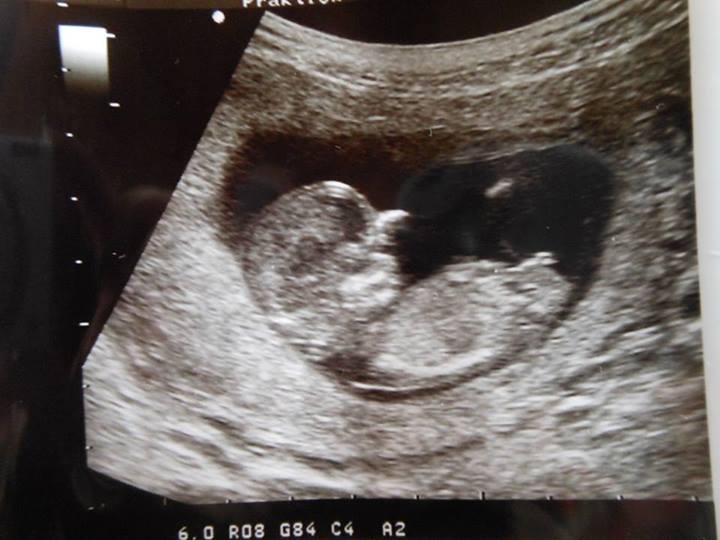

Guesses please, it's for a friend :)